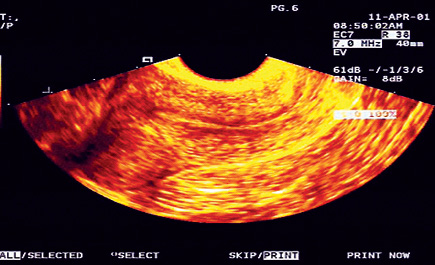

اكياس الشوكولاته في الرحم. أكياس المبيض تتكون على هيئة كتل تكون داخل الرحم وتسبب الآلام الشديدة للمرأة وقد تسبب مشاكل صحية فيما بعد حيث تتحول إلى أورام سرطانية لذلك يجب فحص دوري للمبيض. وتصيب أكياس الشوكولاتة من هم في عمر 20 40 سنة بنسبة أكبر ولكن هذا لا يمنع من الإصابة بها في أي مرحلة عمرية أخرى ولا يوجد سبب واضح وقاطع لبطانة الرحم المهاجرة ولكن هناك عدة أسباب يزداد معها. أكياس المبيض والرحم المائية. تكو ن أكياس على المبيض هو عبارة عن مرض يصيب المبيض لدى المرأة وهو العضو الصغير الذي يتواجد على جانبيالرحم.

تتكون أكياس الشوكولاتة مع كل دورة شهرية ولا توجد أكياس شوكولاتة داخل الرحم لأن الدم يخرج أول ا بأول في. بطانة الرحم المهاجرة يمكن تشخيصها في ٢٤ ٥٠ من السيدات اللاتي تعاني من العقم وأكثر من ٢٠ من الن س اء اللاتي تعاني من آلام الحوض المزمنة. اكياس الشوكولاته في المبيضين أو في أماكن أخري. من المهم أن نتذكر أن أورام بطانة الرحم لا تسبب العقم حتم ا في الواقع بعض النساء اللاتي يعانين من التهاب بطانة الرحم المهاجرة في مرحلة متقدمة مع وجود أكياس الشوكولاتة وتستطيع الحمل.